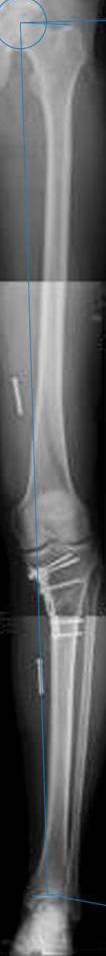

картинки оперированного пациента 40 лет, травма в 2006 году.

оперирован 06.11.2009г - корригирующая остеотомия большеберцовой кости.

Я картинку собрал с некоторыми погрешностями, если провести отвес от центра вращения головки бедра до середины голени (на пациенте),то имеется небольшой вальгус (гиперкоррекция)конечно она (гиперкоррекция) не достигает 10 гр, но 5 гр она достигает.

Проблема как сделать рентгеновские снимки а потом их совместить правильно, кто знает как решить этот вопрос. Ведь стандартные размеры рентгенкассет, оснащенные наши стационары отснять всю конечность с трех попыток!

Уважаемый д-р Батал Шушания,

К сожалению, не очень удачный пример. Если верить Р-граммам, имеет место быть дисплазия мыщелков бедренной кости с наклоном суставной линии. Это уже создает сложности получения хороших отдаленных результатов. Кроме того, по классике, необходима гиперкоррекция с созданием вальгуса 7-10 градусов для максимальной разгрузки медиального отдела КС. Если верить укладке, то линия сустава имеет четкий варусный наклон, поэтому результат операции м.б. кратковременным. В этих случаях показана двойная остеотомия бедра и тибии.

Впечатление искажает неправильная укладка.

Если сделать правильно, то видно, что бедренная кость в порядке, а цель остеотомии (низкой, кстати), не достигнута вовсе.

Сохраняется варус. Для того, чтобы создать вальгусную гиперкоррекцию, не моделируя при этом откровенный Х голени, можно сделать медиализирующую остеотомию.